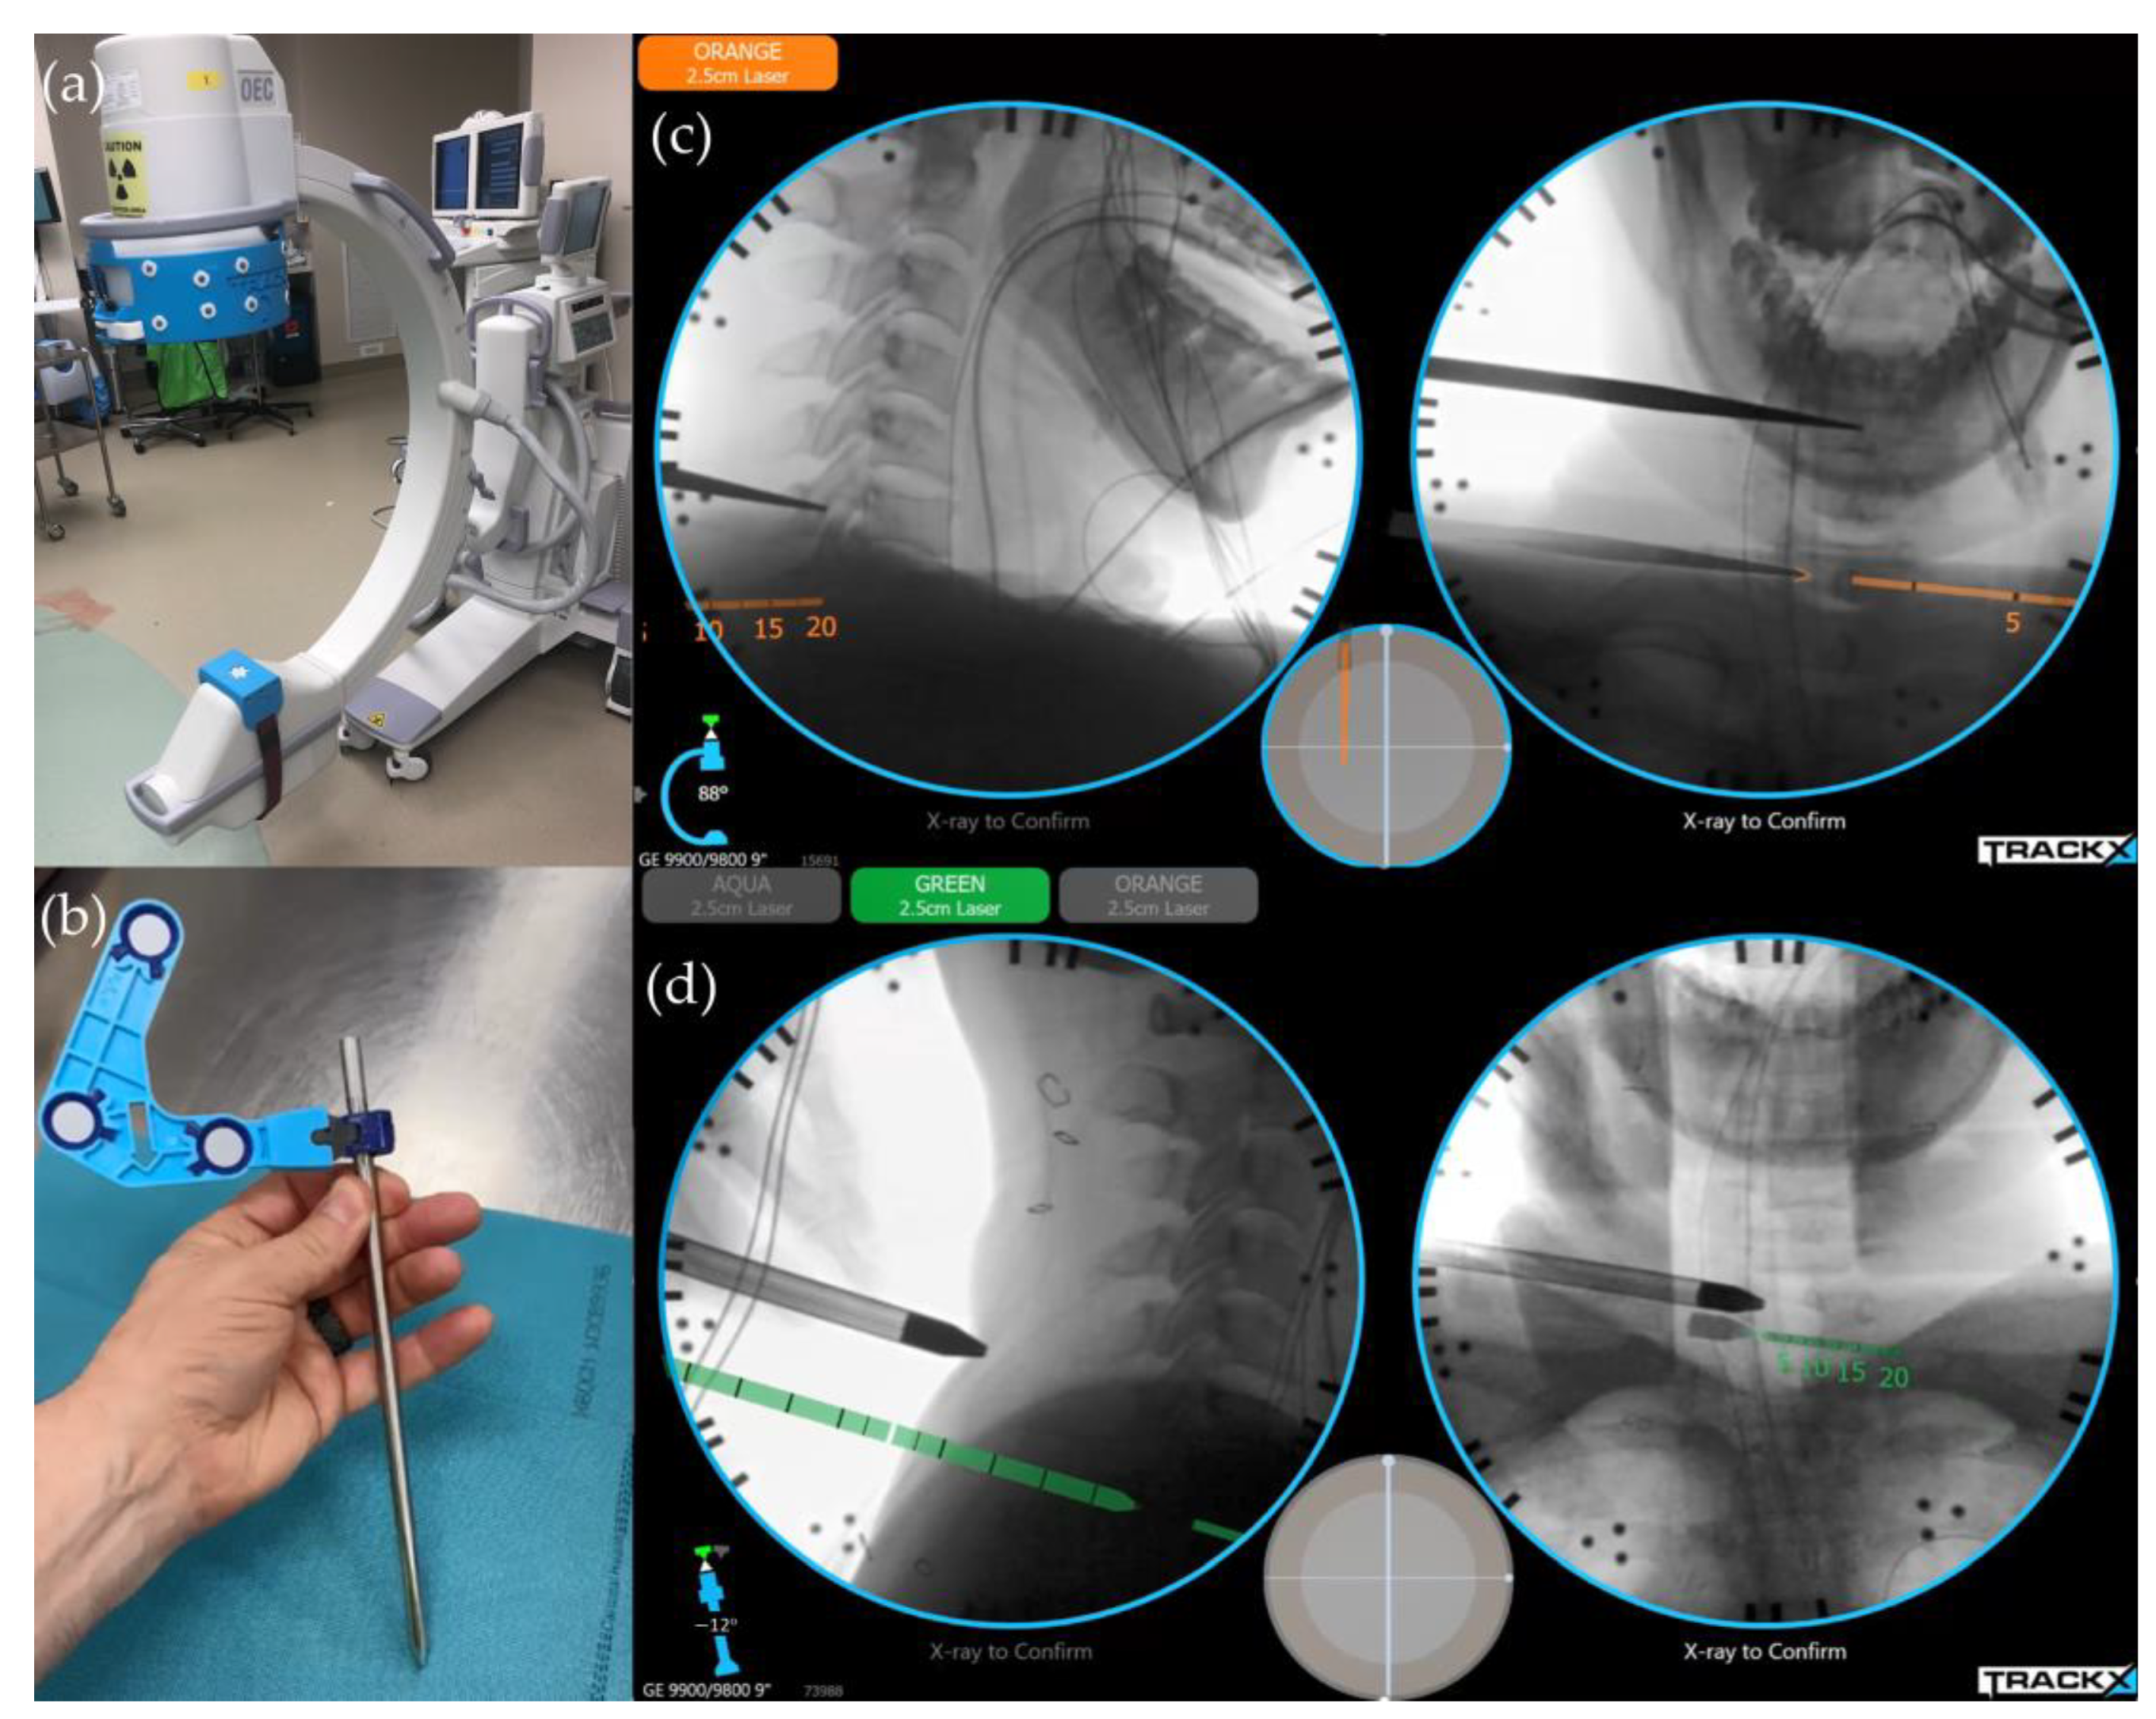

6.1. Image-Guided Navigation System/Instrument Tracking System